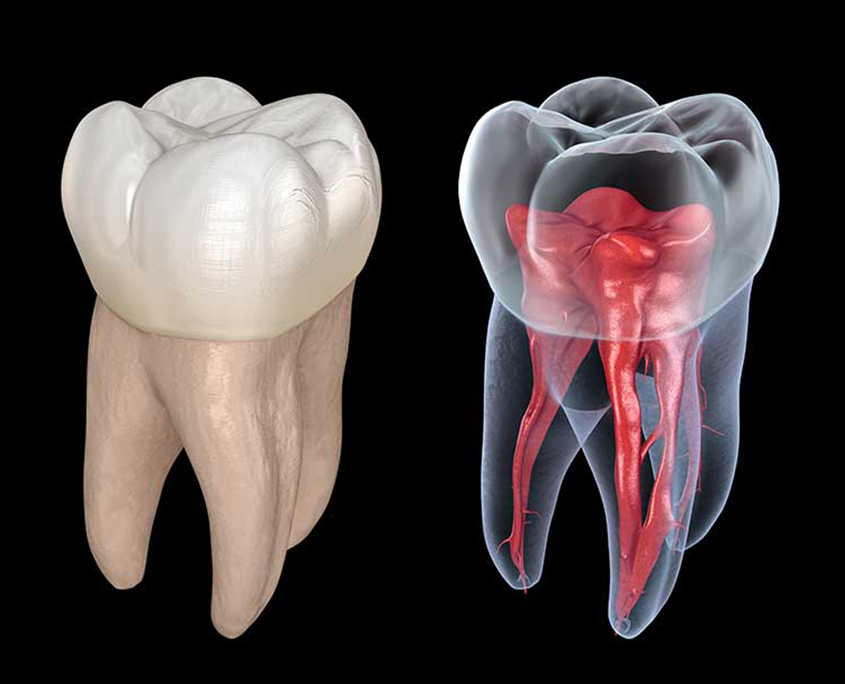

Dental anatomy and morphology

Micro-CT is a powerful tool for studying the anatomy and morphology of the teeth and jaws. It can be used for the study of dental development and eruption, providing important information about the timing and sequence of tooth eruption, as well as the development of the dental arch. Additionally, micro-CT can be used for comparative dental anatomy, providing information about the evolution of teeth and the functional morphology of dental structures in different species.

- Tooth morphology analysis: Micro-CT can be used to analyze the internal and external morphology of teeth, including the roots and pulp cavities. This information is helpful in understanding tooth development and studying dental pathologies.

- Enamel analysis: Micro-CT can be used to analyze the thickness and mineral content of enamel, which is important for understanding the mechanical properties of teeth and for studying enamel-related diseases such as enamel hypoplasia.

- Dentin analysis: Micro-CT can also be used to analyze the structure and density of dentin, which is important for understanding the mechanical properties of teeth and for studying dentin-related diseases such as dentinogenesis imperfect.

Dental imaging and diagnosis

Micro-CT is a powerful tool for high-resolution dental imaging, providing detailed information about the anatomy and structure of the teeth and jaws. It can be used for quantitatively assessing dental caries, providing important information about the extent of decay and the efficacy of different treatments. Additionally, micro-CT can be used to diagnose endodontic pathologies, such as root canal infections, by visualizing the internal structures of the teeth in 3D.

Endodontic Treatment Evaluation

Micro CT can be used to evaluate the success of endodontic treatments such as root canal therapy. Researchers can use these images to study the anatomy of the root canals and to assess the effectiveness of the treatment in terms of sealing the canals and preventing reinfection.

- Root canal analysis: Micro-CT can be used to analyze the internal structure of root canals, allowing researchers to evaluate the efficacy of endodontic treatments and develop new treatment modalities.